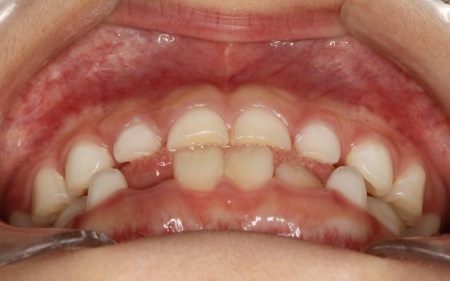

9歳女の子 反対咬合を顎の成長を利用した矯正装置を用いて改善した症例

治療前

はじめの相談内容 「受け口を治したい」とご相談いただきました。

診断結果 拝見したところ、患者様は乳歯のみが生えている乳歯列期の段階でしたが、この時点ですでに反対咬合が認められました。

反対咬合とは、下の前歯が上の前歯よりも前に出ている状態のことで、一般的に「受け口」とも呼ばれます。

反対咬合は、このまま放置すると永久歯に生えかわったあとも継続してしまうおそれがあり、顎の成長や噛み合わせ、発音や顔貌にも悪影響を及ぼすことがあります。

しかし、この時期は顎の骨が成長段階にあり、適切な治療を行うことで改善が期待できるため、早期に治療を開始する必要があると診断しました。